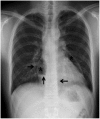

Pneumopericardium is a rare complication of pericardiocentesis, occurring either as a result of direct pleuro-pericardial communication or a leaky drainage system. Air-fluid level surrounding the heart shadow within the pericardium on a chest X-ray is an early observation at diagnosis. This clinical measurement and process is variable, depending on the hemodynamic status of the patient. The development of a cardiac tamponade is a serious complication, necessitating prompt recognition and treatment. We recently observed a case of pneumopericardium after a therapeutic pericardiocentesis in a 20-year-old man with tuberculous pericardial effusion.